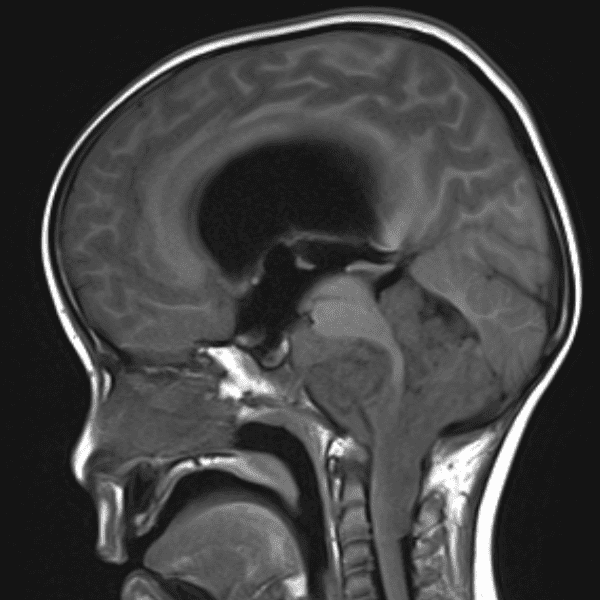

Classic Cases